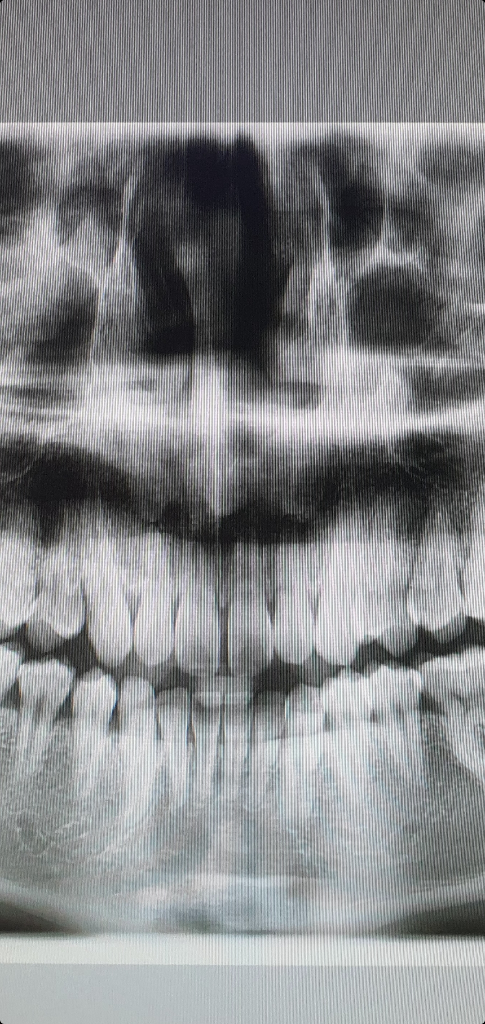

교정 전 사진입니다!

아래쪽 앞니가 특히 많이 휘었는데 교정치과에서는 괜찮다고 계속 진행해도 된다고 하네요.

이게 정상이 맞나요?

• 2번 째 사진

교정을 한다고 뿌리가 휘거나 그렇진 않습니다. 사진상 약간의 오류처럼 보입니다. 크게 문제가 잇어 보이진 않습니다.